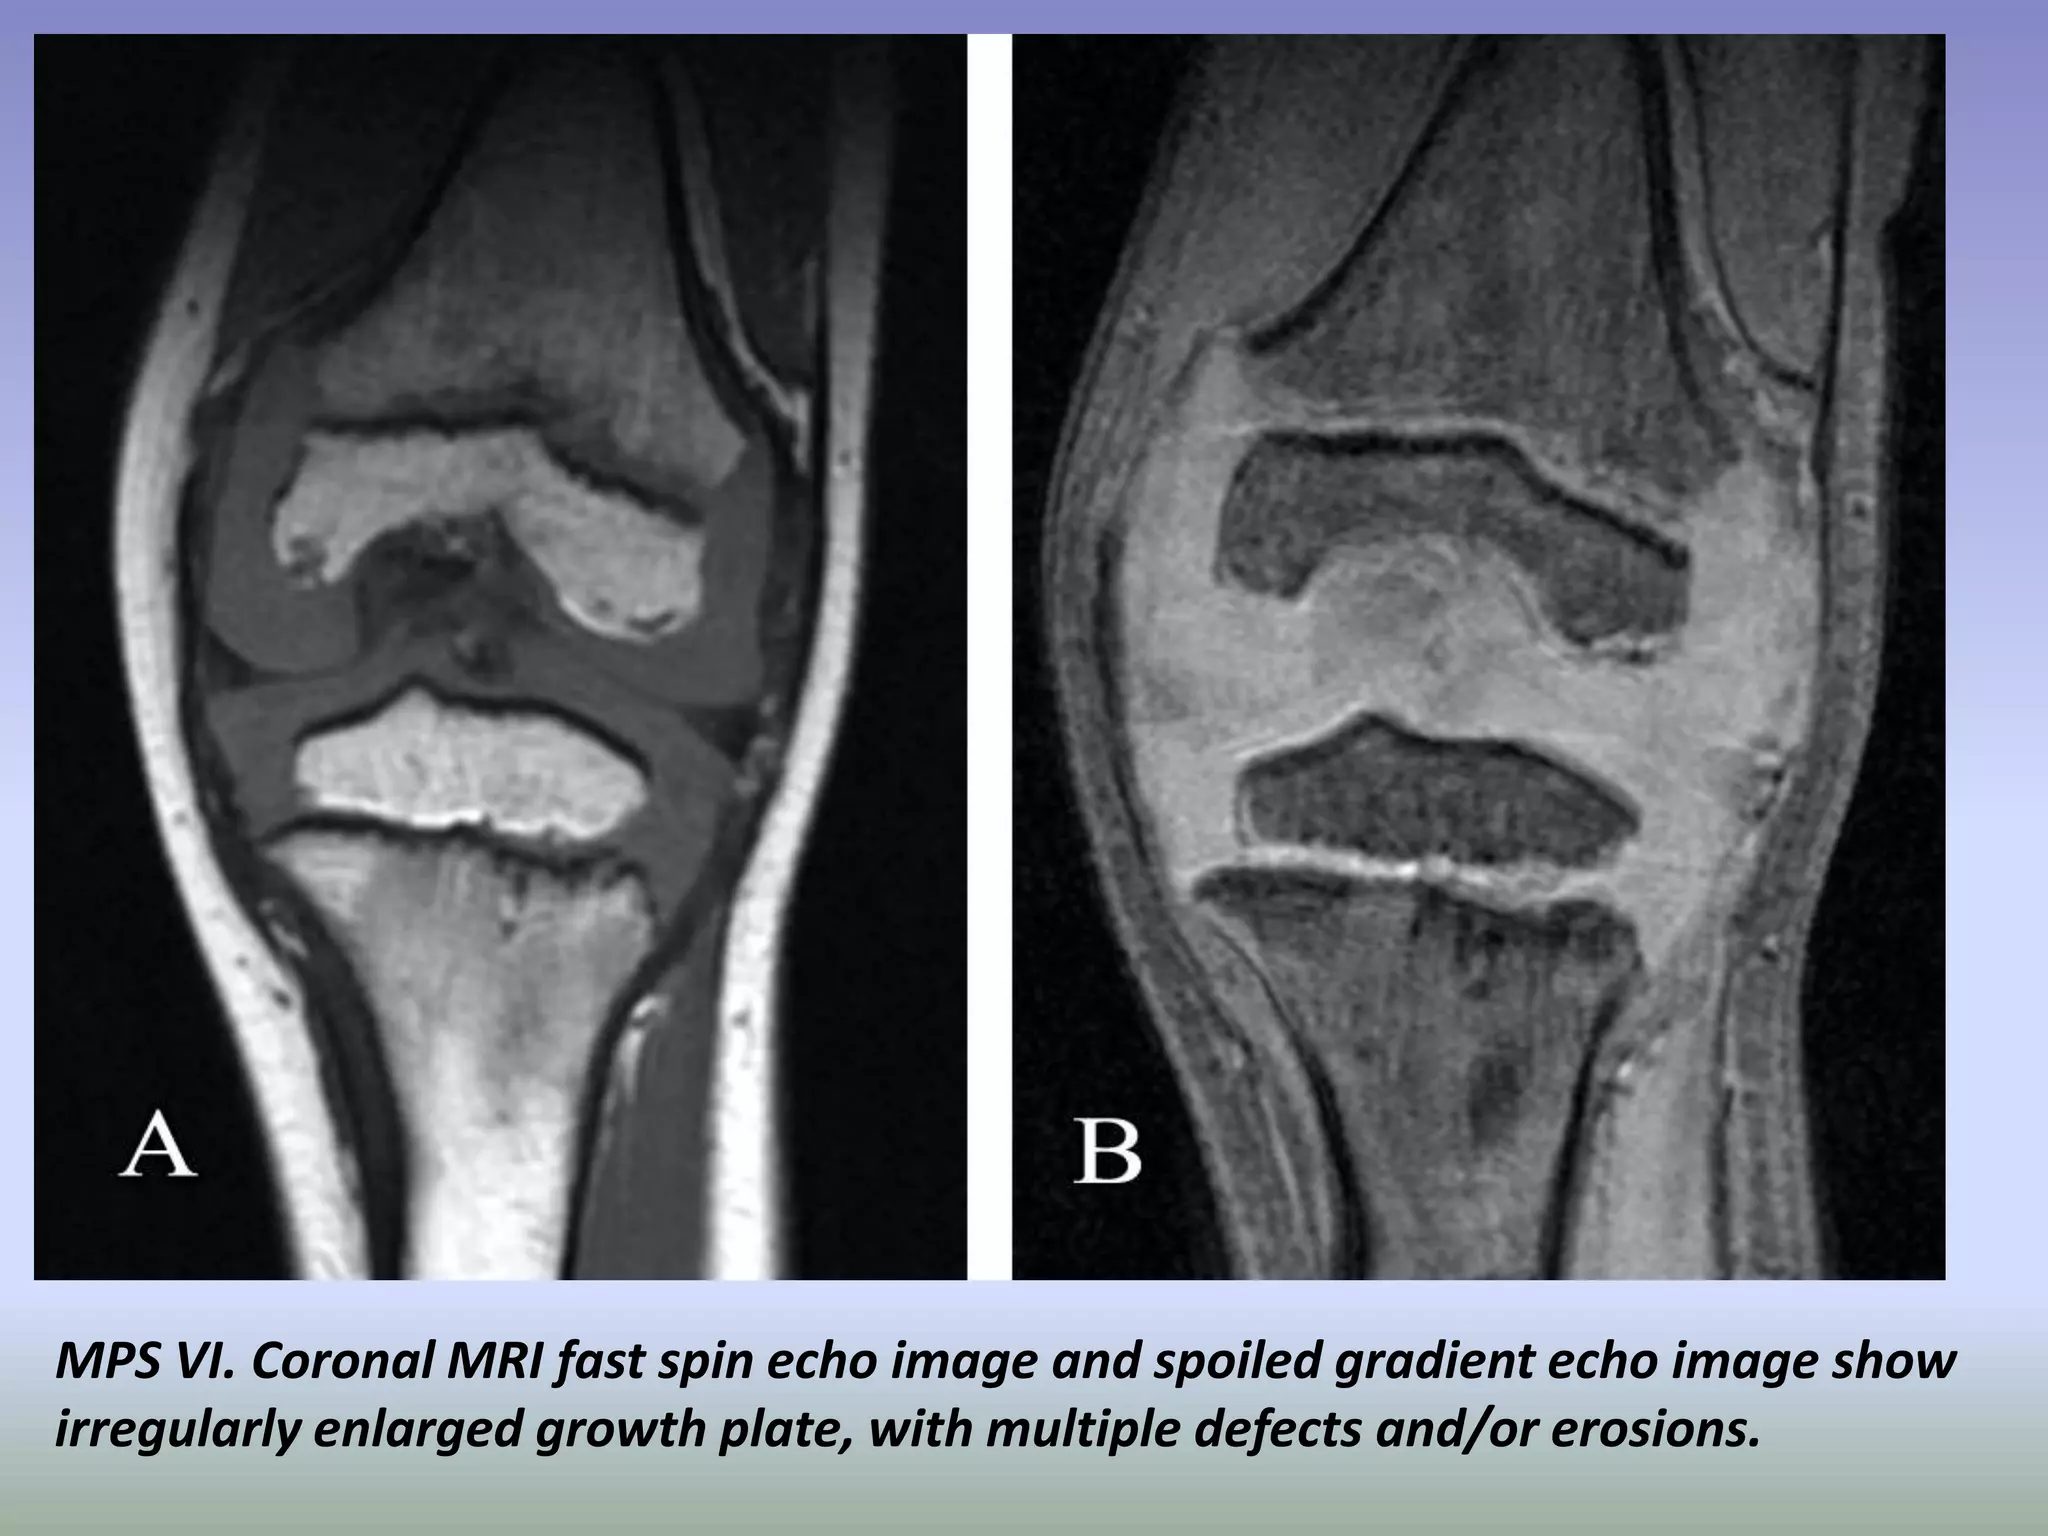

MPS VI. Coronal MRI fast spin echo image and spoiled gradient echo image show

irregularly enlarged growth plate, with multiple defects and/or erosions.